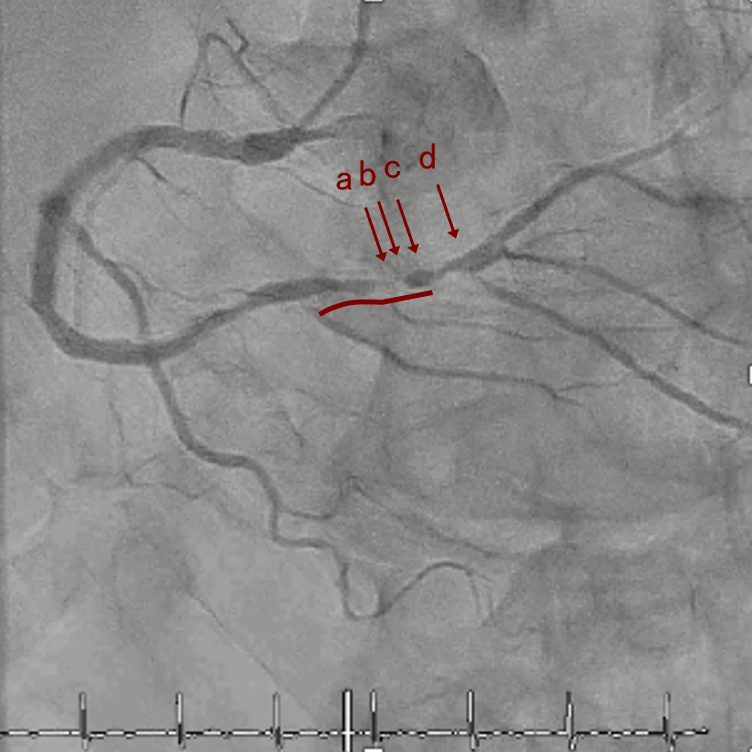

CAG

RCA distalの高度石灰化狭窄病変

IVUSでは8時方向からPD枝がはいいてくる。

PreのIVUSではaの部位のみlipid plaqueを認め削ることでdistal embolismのリスクがあり、そのほかは270度の偏心性石灰化であるがwire biasは良好。

OAS low speedによる引きを赤線の区間行う方針とした。

OAS low speedによる引きのsandingを3回行いIVUSを確認するとa-cでは心筋側側へのOASによる良好なbias変化と、それに伴いdの健常側への危険なbias変化を認めた。

そのためcでIVUSマーキングを行い、その点より引きで赤線のpinpoint OAS high speedを行い、dに関してはinjury回避のためにOASを当てない方針とした。

OASを行うたびに徐々に心筋側側にwire bias変化をきたし、石灰化病変部に関してはそれが良い変化となっているが、distal reference (d) に関してはinjury riskの高いbias変化となっていった。

Pre

OAS low3

OAS high3

Cutting2.5mm